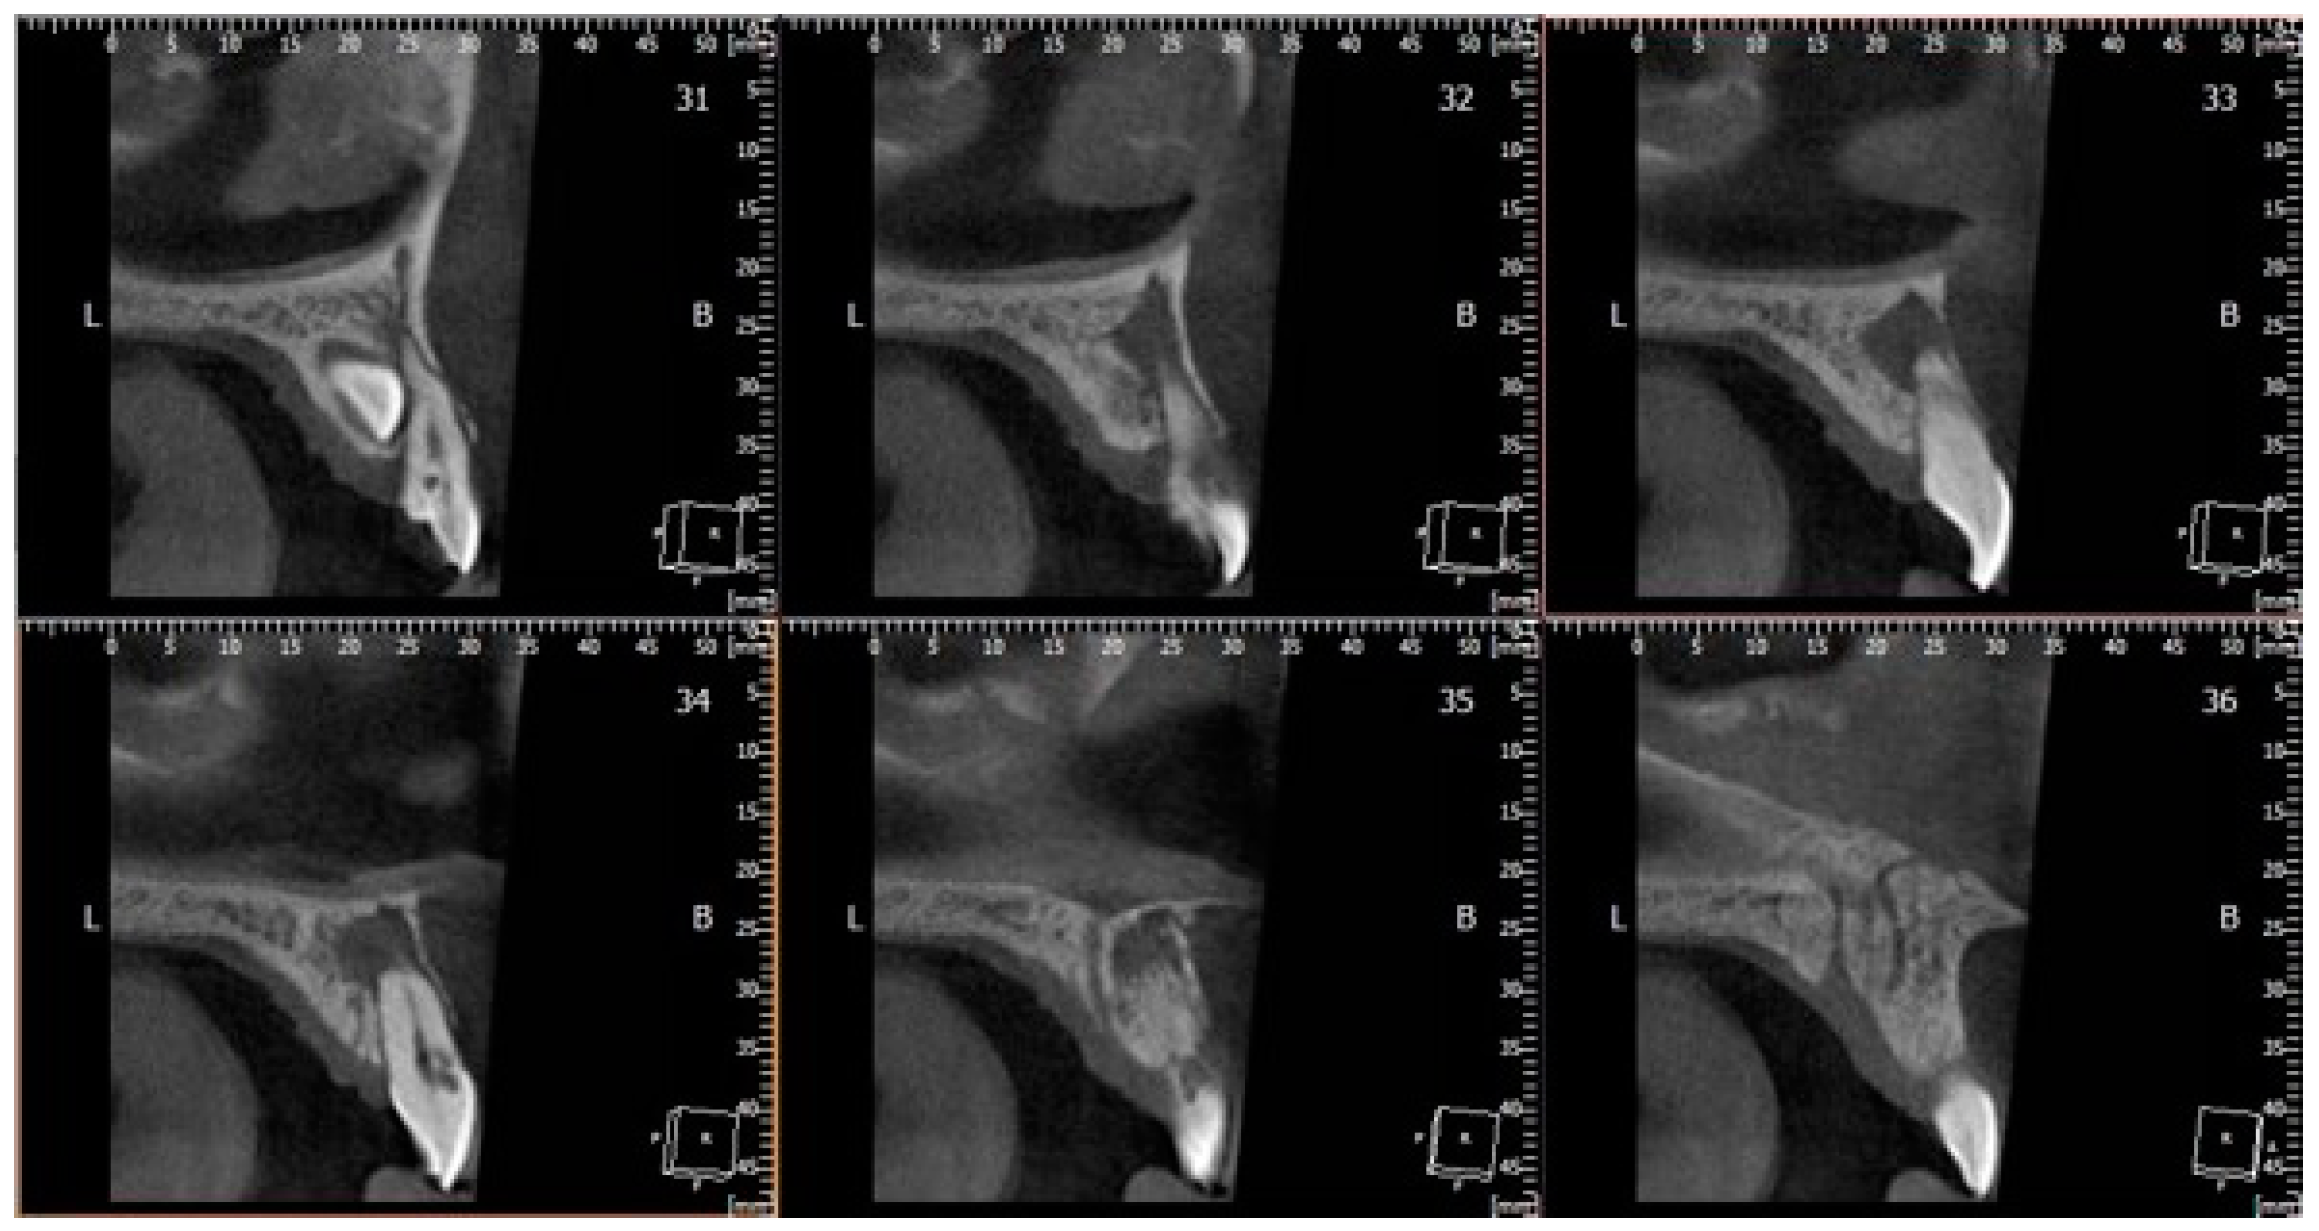

2. Case Report